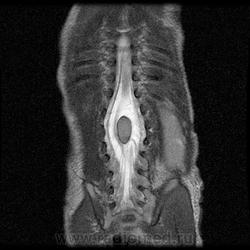

Диастематомиемия.

wikimedia

В обоих случаях перегородка имеет переднезаднее направление, но может располагаться не строго в сагиттальной плоскости и не всегда делит спинной мозг на равные части. У многих пациентов имеется выраженная асимметрия развития половин спинного мозга, вплоть до гипоплазии одной из них. Перегородка может располагаться в любом отделе позвоночника. Чаще она встречается в поясничном отделе на уровне L2-L4 сегментов, реже - в грудном, еще реже - в шейном (в последнем случае практически всегда сочетается с синдромом Клипеля – Фейля). Формирование двух и более перегородок в разных отделах позвоночника наблюдается очень редко.